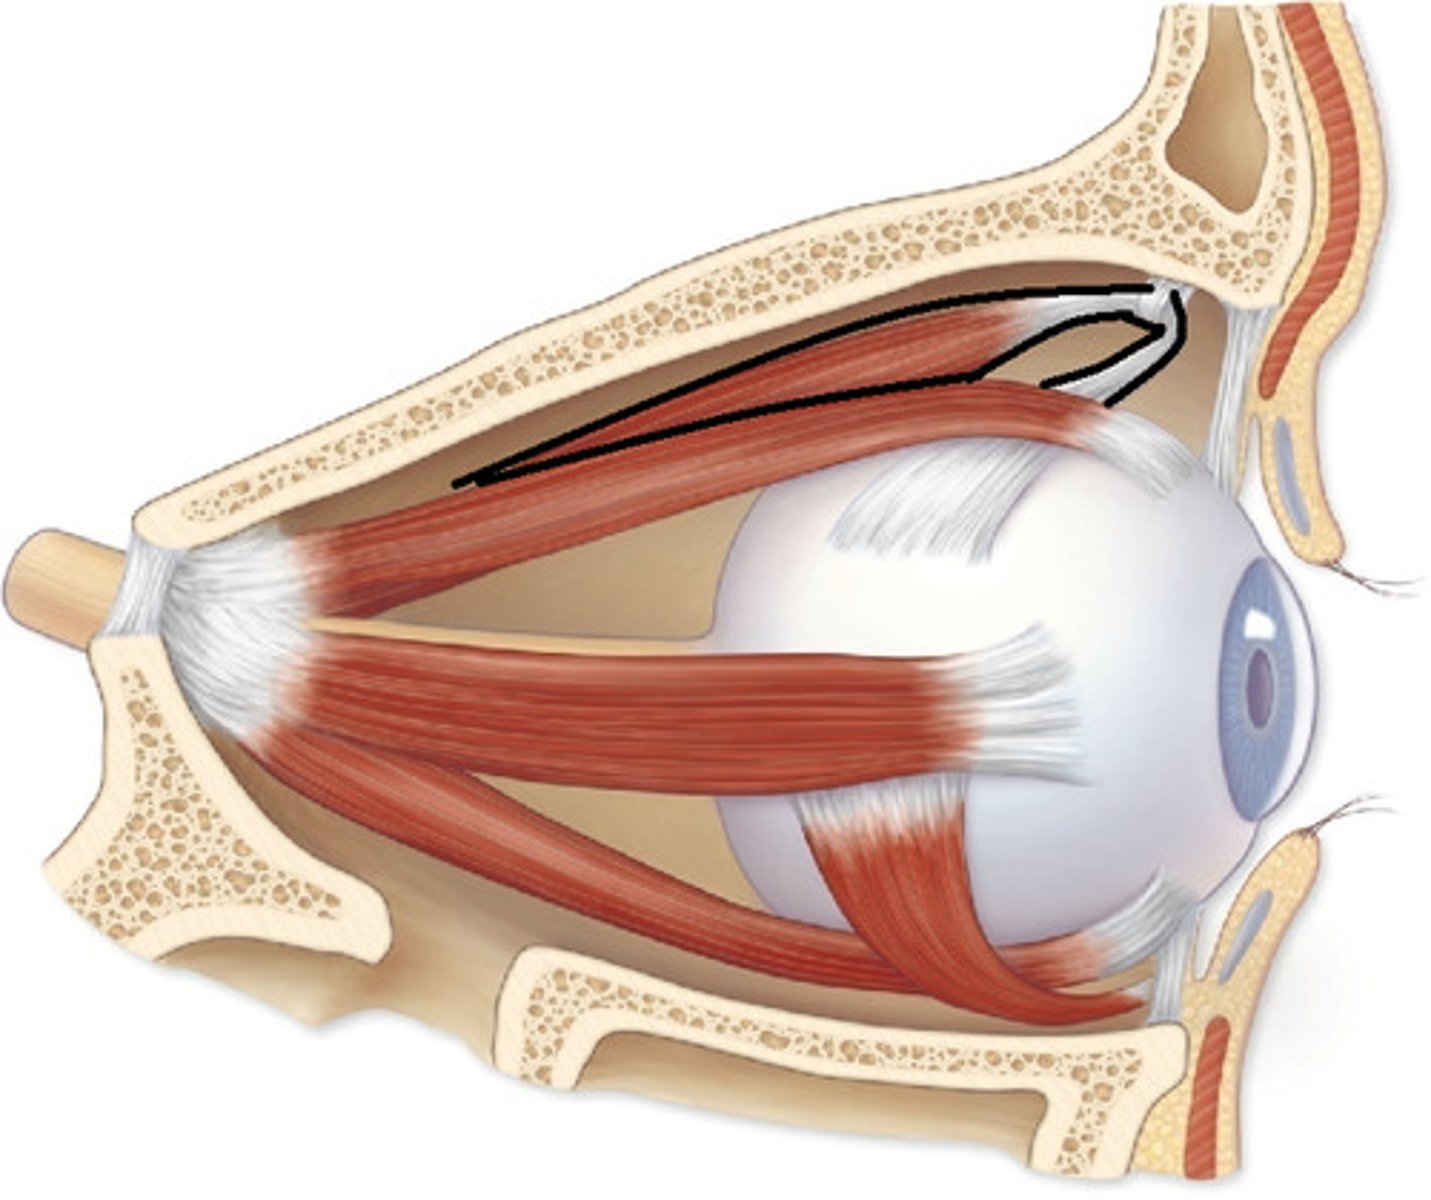

Superior Oblique

Superior Rectus

Inferior Rectus

Lateral Rectus

Medial Rectus